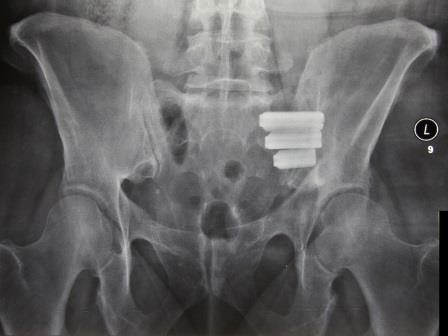

Der Eingriff erfolgt unter Vollnarkose und fluoroskopischer Kontrolle. Zunächst wird eine ca. 3 cm lange Inzision zwischen Beckenkamm und Trochanter major vorgenommen. Durch diese wird ein Führungsdraht quer zum Iliosakralgelenk eingeführt und ein weichteilschützendes Kanülensystem angebracht. Nach durchgeführter Tiefenmessung und entsprechender Bohrung wird das Implantat über das Kanülensystem eingebracht. Diese Schritte werden für die zwei weiteren Implantate wiederholt, sodass die Implantate eine zueinander parallel angeordnete Verbindung des Kreuzbeins und Darmbeins bilden (Abb. 1). Anschließend wird die Inzision verschlossen.